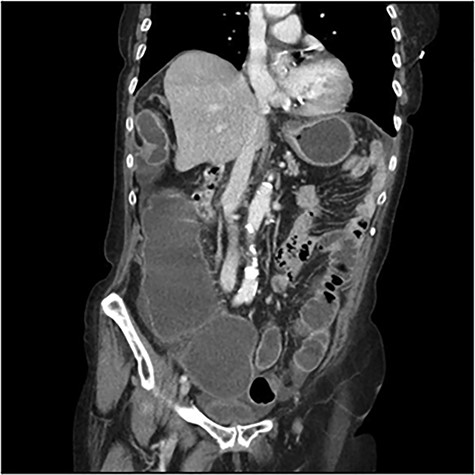

The scanner demonstrated a colonic occlusion resulting from an incarceration, which was diagnosed as a hernia of Bochdalek containing the hepatic angle of the colon (Fig. 2–4).

: CT scan images demonstrating a right diaphragmatic hernia containing intestine.

CT scan images demonstrating a right diaphragmatic hernia containing intestine.